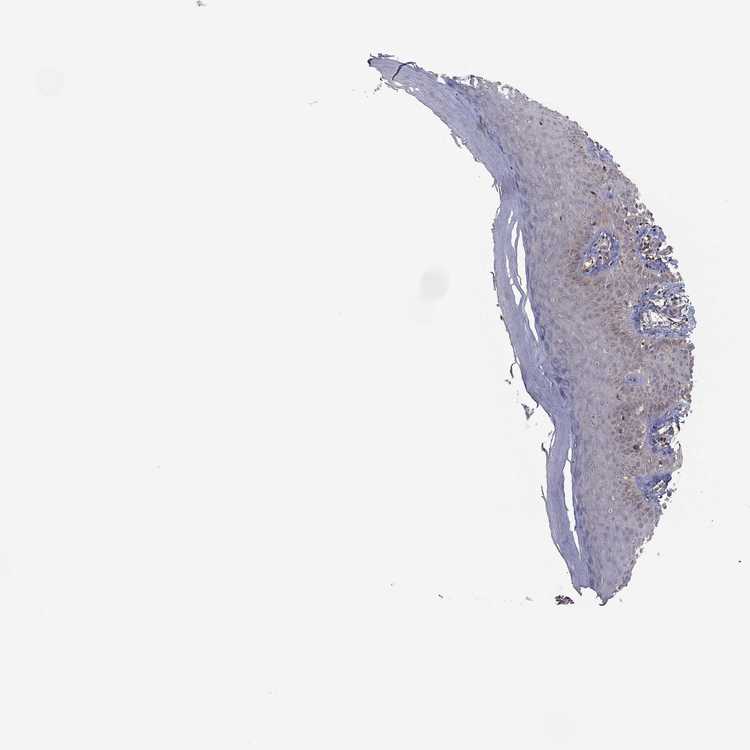

SKIN 1 - Antibody stainingi

Antibody staining in the annotated cell types in the current human tissue is reported as not detected, low, medium, or high, based on conventional immunohistochemistry profiling in selected tissues. This score is based on the combination of the staining intensity and fraction of stained cells.

Each image is clickable and will lead to virtual microscopy that enables deeper exploration of all samples and also displays staining intensity scores, fraction scores and subcellular localization as well as patient and tissue information for each sample.

Antibody HPA074389

Langerhans Not detected

Fibroblasts Not detected

Keratinocytes Not detected

Melanocytes Not detected

SKIN 2 - Antibody stainingi

Antibody HPA067906Antibody HPA074389

Epidermal cells MediumNot detected